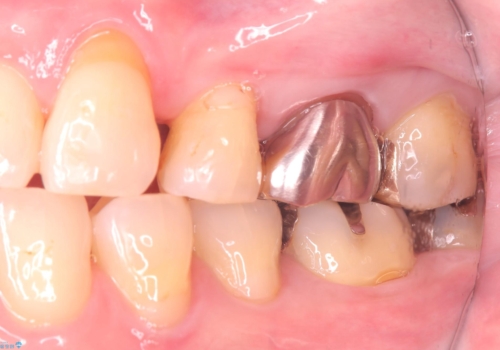

- 主訴:フロスを通したら、詰め物が取れた。適合の良いものを入れたい。

保険適用のメタルインレーが脱離しており、適合重視・咬合力が強いことからゴールドインレーでのやり替えとなりました。

フロスを通しインレーが脱離したことから、インレーと歯質との境に段差(適合不良)があった可能性があり、適合の良さや咬合力による補綴物の破折リスクを考慮し、ゴールドインレーでのやり替えとなりました。